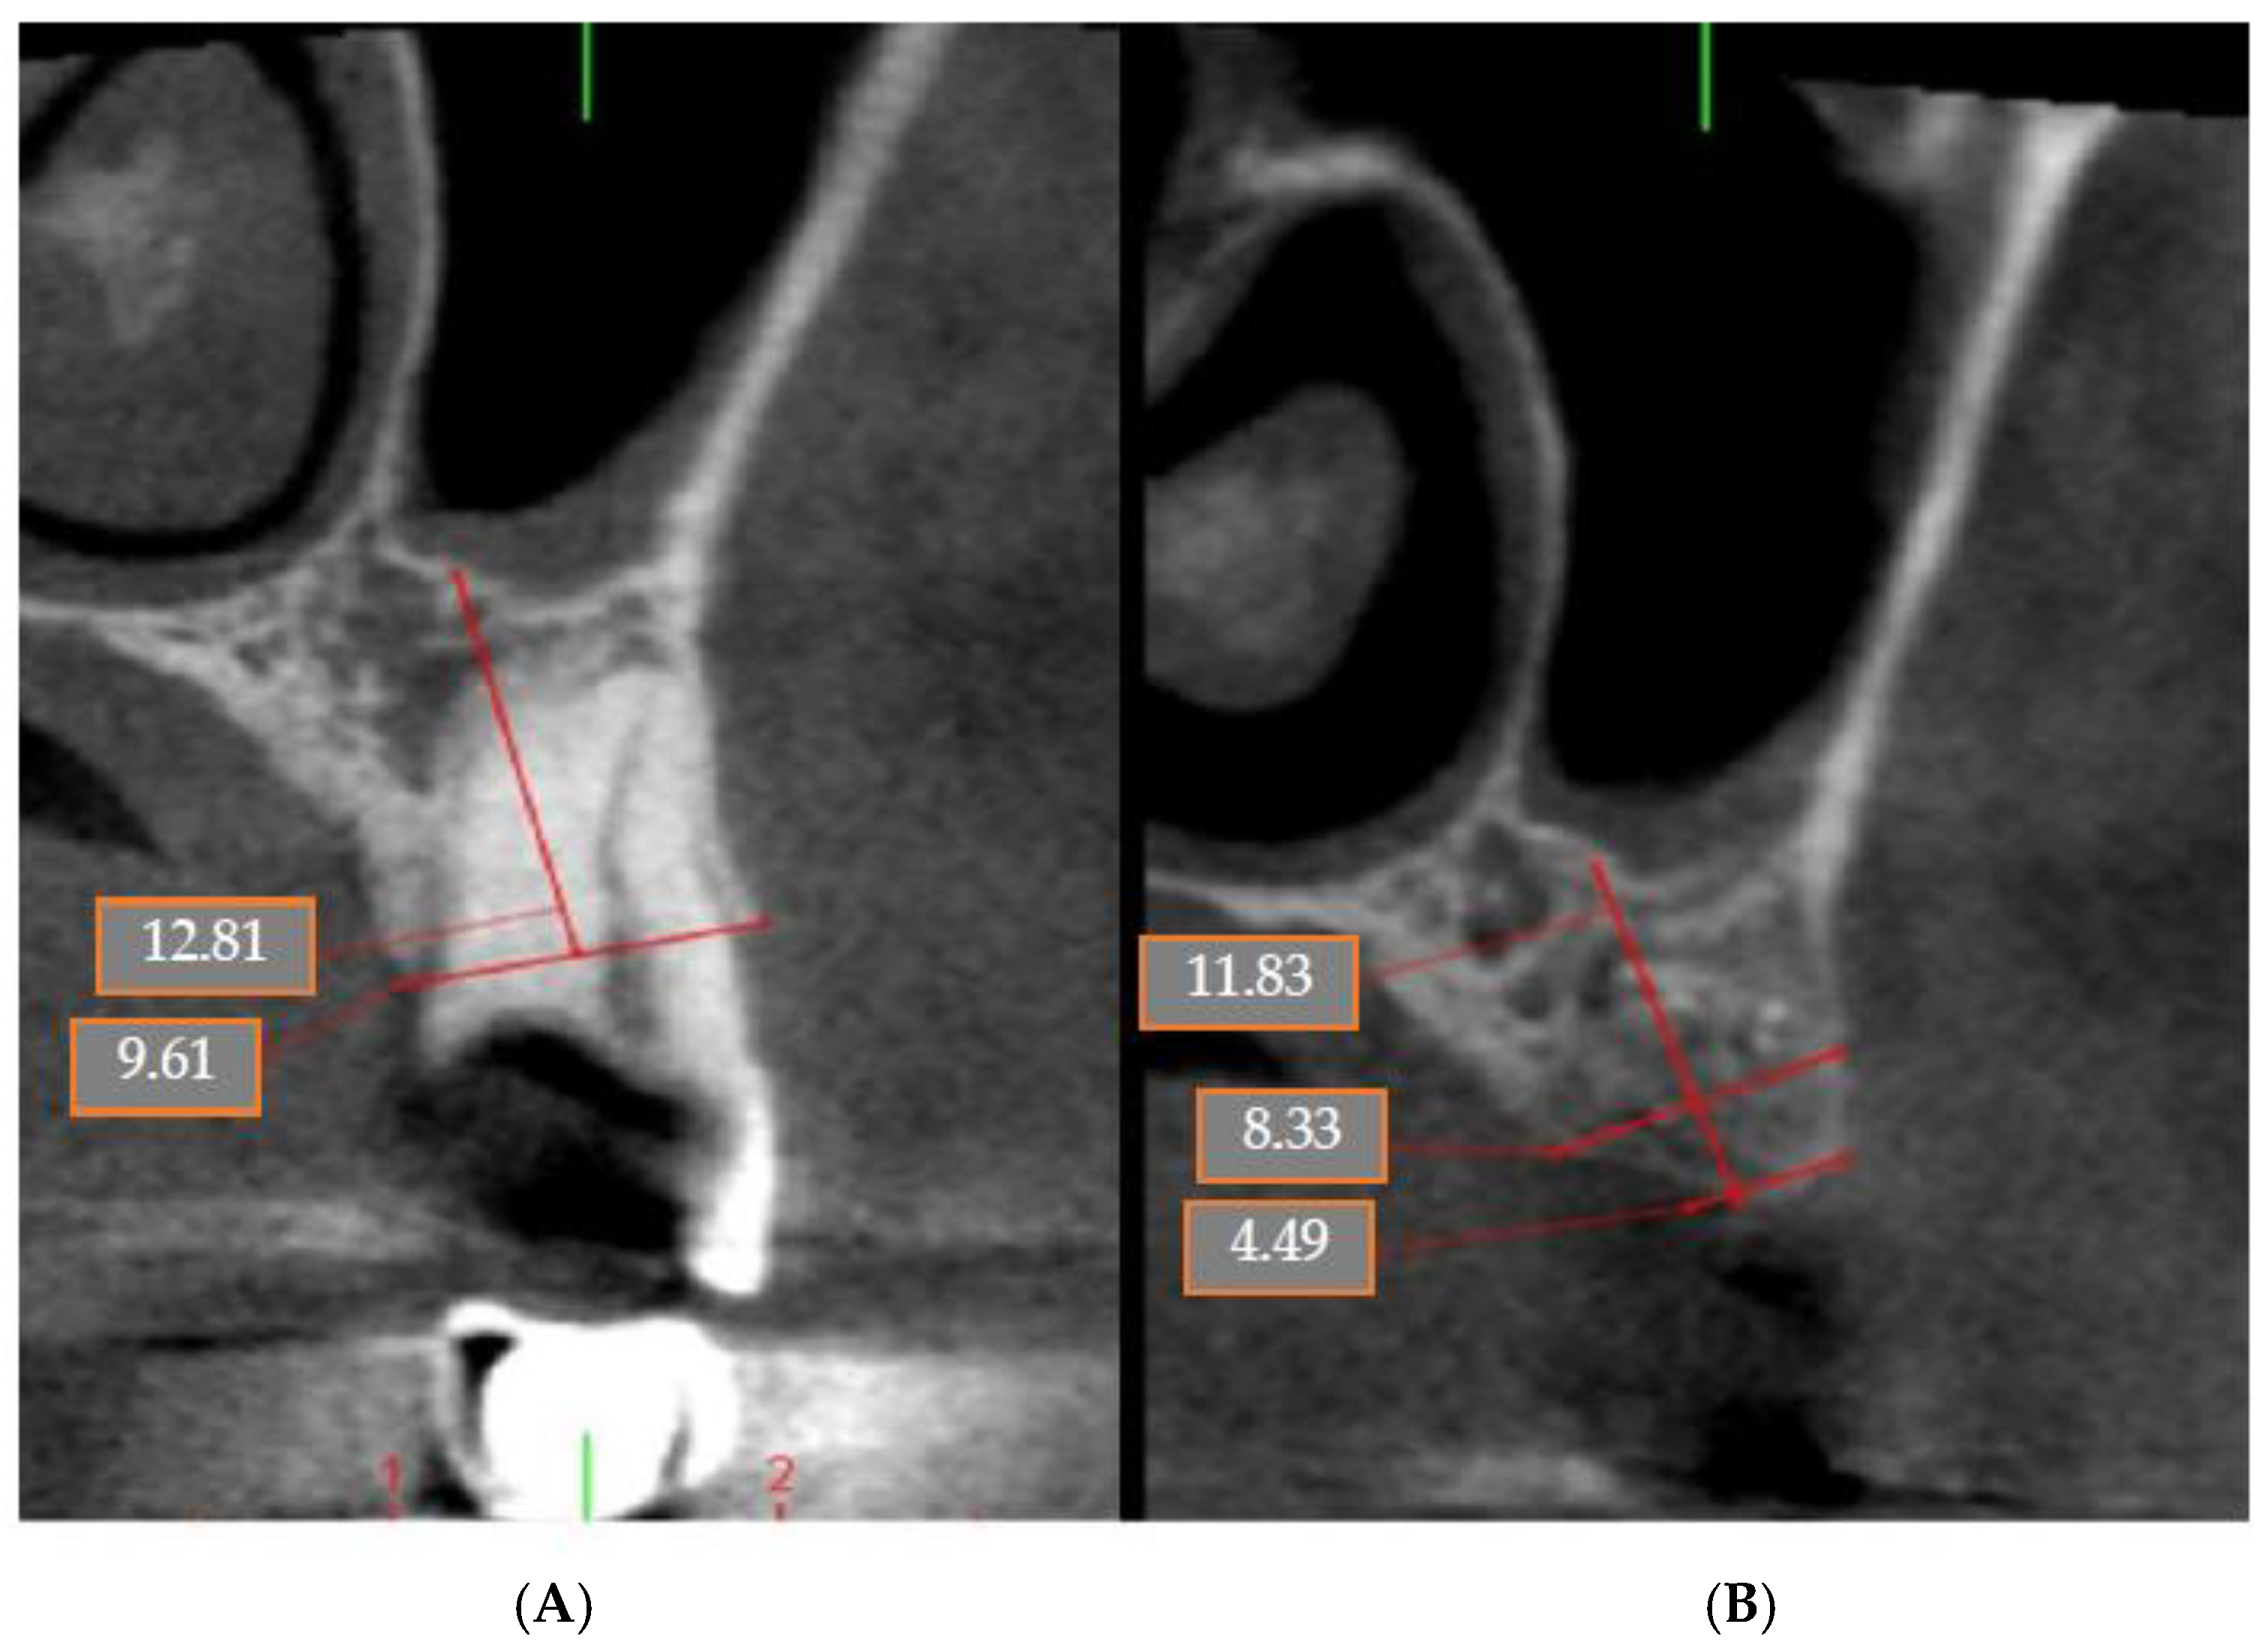

4.5. Patient No.5

4.6. Patient No.6